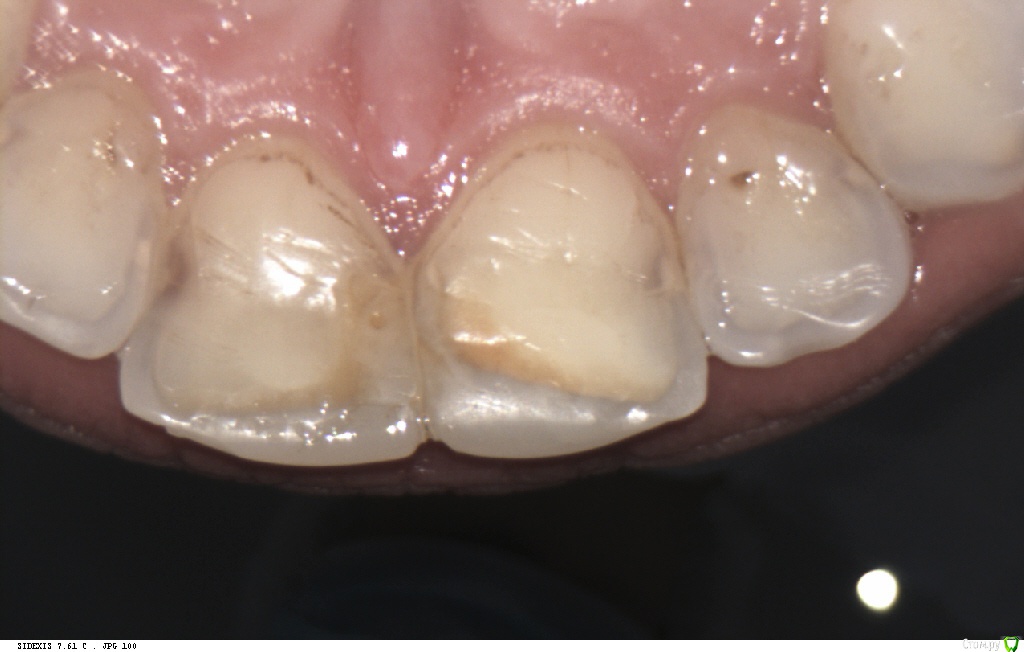

Pan Опубликовано 6 мая, 2017 Поделиться Опубликовано 6 мая, 2017 (изменено) типичная локализация кариеса при плохой гигиене и злоупотреблении в питании фастфуда. Ну понятно, что всё это на фоне сниженной кариесрезистентности. Первым делом нужно объяснить девушке значимую роль питания и гигиены в развитии кариозных процессов. Изменено 6 мая, 2017 пользователем Pan 1 Ссылка на комментарий

St. Опубликовано 9 мая, 2017 Поделиться Опубликовано 9 мая, 2017 Принесла анализы и заключения специалистов.как оказалось пару месяцев назад обследовалась. Практически космонавт)) Слегка увеличена щитовидка, но гормоны в норме. Газировку и фреши не пьет, фастфуд не ест. Так ничего не беспокоит кроме внешнего вида.Озвучили вариант терапевтического лечения сиц+рем.терапия ивариант тотала, ушла думать.Как думаете тотал может решить вопрос или есть высокая вероятность вторичного поражения? Ссылка на комментарий

Л Ю С Я Опубликовано 10 мая, 2017 Поделиться Опубликовано 10 мая, 2017 Как думаете тотал может решить вопрос или есть высокая вероятность вторичного поражения?Если все сделано по феншую , почему бы нет. Главное, чтоб с гигиеной было все окей и стабилен пародонт Ссылка на комментарий